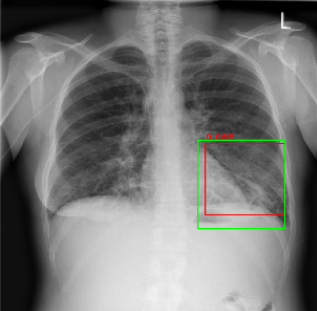

Detection of High-Grade Small Bowel Obstruction on Conventional Radiography with Convolutional Neural Networks

Studies of deep learning applied to abdominal radiographs. We show that transfer learning can be used to create a classifier for detection of high-grade small bowel obstruction patterns on supine abdominal radiographs.

Phillip Cheng, Tapas Tejura, Khoa Tran, Gilbert Whang

Abdominal Radiology 2018 (pilot study)

Am J Roentgenology 2019 (increased training)

2018 RSNA Pneumonia Detection Challenge

I submitted the 3rd place entry in an international machine learning competition for detection of pneumonia on chest radiographs. The competition was organized by the Radiological Society of North America (RSNA) and the Society of Thoracic Radiology, and hosted on Kaggle. My solution used an ensemble of RetinaNets.

Phillip Cheng

Am J Roentgenology 2019